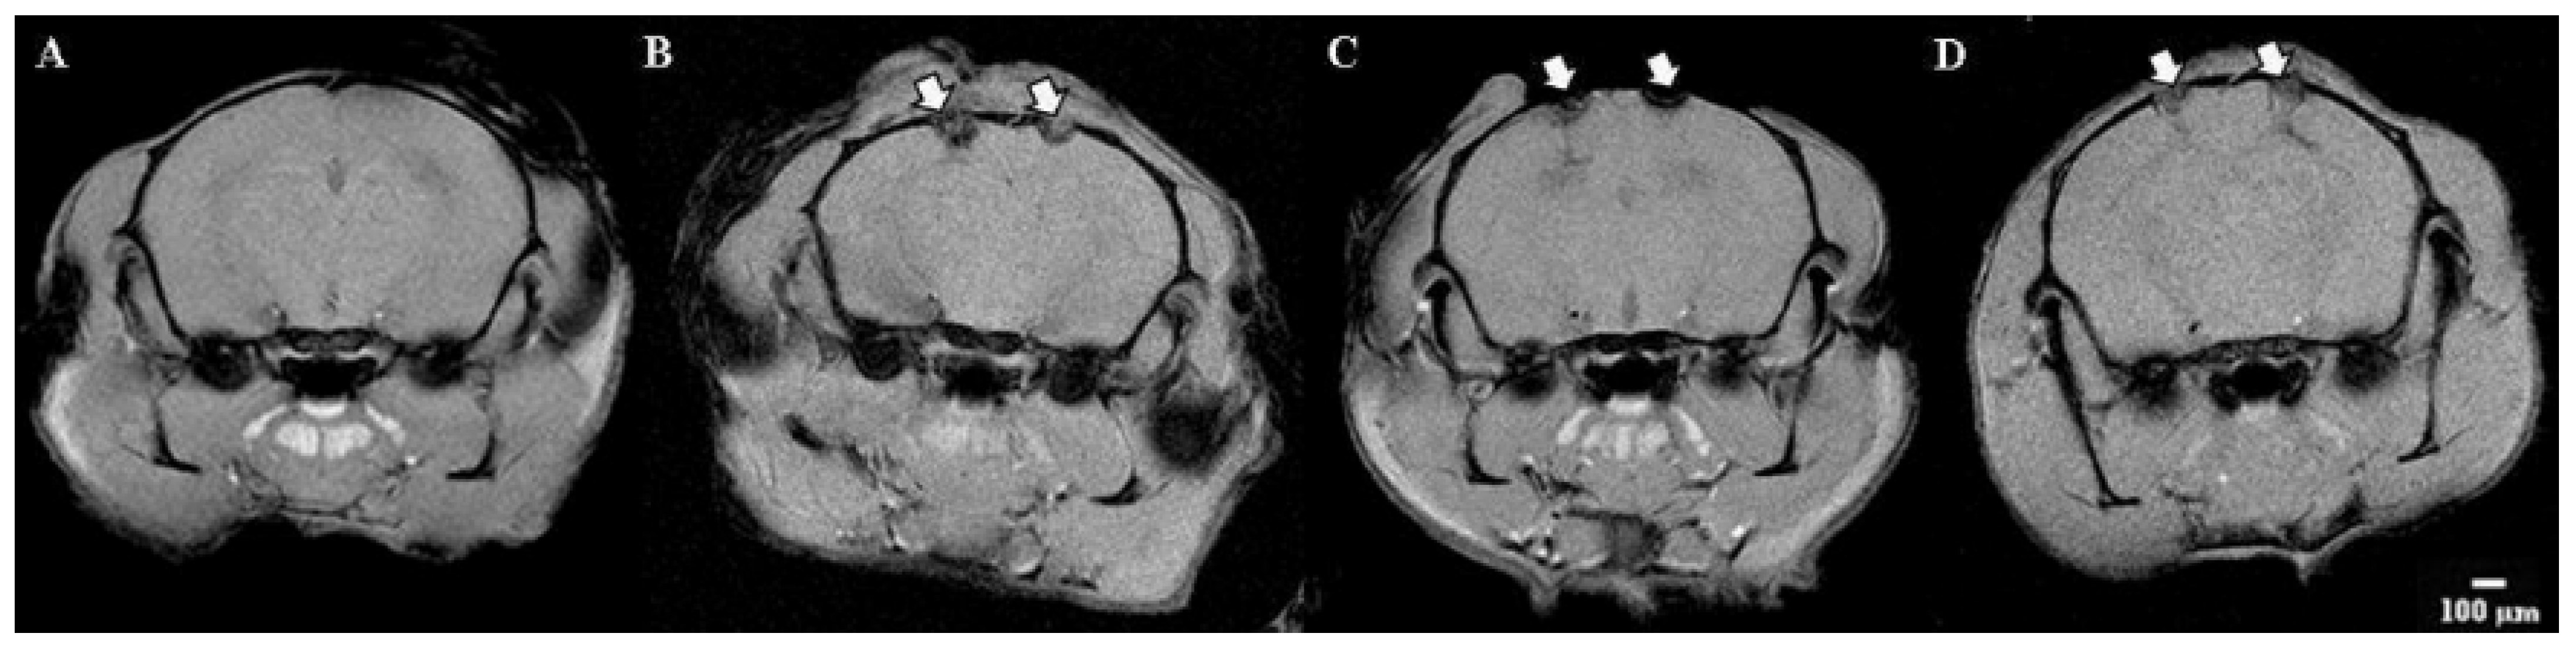

Visualization modeling of ischemia was performed on the 7th day using magnetic resonance imaging. An analysis of the structures of the brain was carried out. Particular attention is paid to the volume of the focus of ischemic inflammation.

Tomographic images of the brain of the group of Intact animals did not reveal any disorders—the cerebral hemispheres have a normal structure and intensity of the MR signal (differentiation of gray and white matter).

MRI images of the Control group demonstrate pronounced areas of edema in the areas of the sensorimotor cortex and ventricles of both the left and right hemispheres. The volume of the affected area was 28.5 ± 7.51 mm3 (Figure 9).

Significant changes in brain tissue were noticeable when the IKKβ kinase inhibitor was applied. By day 7 of the postischemic period, the pronounced structural changes in the area of the cerebral cortex with a predominance of diffuse edema were observed. The edema smoothly passed to the ventricles and further into the deep layers of the nervous tissue. In this group, there was the largest volume of the affected area (38.6 ± 18.8 mm3), while the width of the affected area was also at 6–7 mm maximum.

The response of the nervous tissue to the SRC kinase inhibitor was similar to the IKKβ kinase blockade; however, in this group, there was a less diffuse influx of fluid into the area of ischemic injury. The volume of the affected area was 35.8 ± 6.2 mm3.

Figure 9. Representative MR-images of the brains of mice in the modeling of acute ischemic brain injury. (A)—Intact, (B)—Control, (C)—SRC inhibitor, (D)—IKKβ inhibitor. Arrows show traces of inhibitor injection.